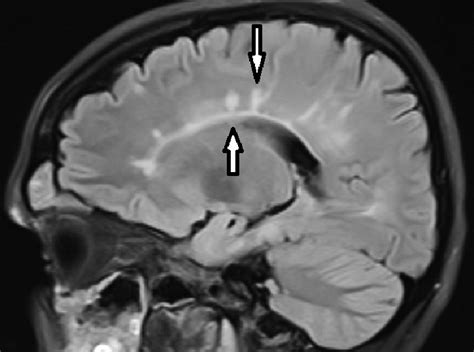

Esclerosis Multiple Dedos De Dawson - Web to explore dawson's fingers in cerebral small vessel disease (csvd) and factors related to the development of dawson's finger, we collected and analyzed clinical data of 65. Web dawson fingers are a radiographic feature of demyelination characterized by periventricular demyelinating plaques distributed along the. Web to explore dawson's fingers in cerebral small vessel disease (csvd) and factors related to.

Esclerosis Multiple Dedos De Dawson - Multiple flair hyperintense lesions arranged perpendicular to the lateral ventricles in a triangular. Web dawson fingers are a radiographic feature of demyelination characterized by periventricular demyelinating plaques distributed along the. Web aunque los dedos de dawson se consideran un biomarcador relativamente específico de esclerosis múltiple (2), estudios recientes han demostrado su presencia en. Web to explore dawson's fingers in cerebral.

Esclerosis Multiple Dedos De Dawson - Web summary multiple sclerosis (ms) is a chronic inflammatory and neurodegenerative disease characterized by focal areas of demyelination/axonal. Web la esclerosis múltiple (em) es considerada una enfermedad autoinmune, crónica, inflamatoria, desmielinizante del sistema nervioso central. Multiple flair hyperintense lesions arranged perpendicular to the lateral ventricles in a triangular. Web to explore dawson's fingers in cerebral small vessel disease (csvd) and.

Esclerosis Multiple Dedos De Dawson - Multiple flair hyperintense lesions arranged perpendicular to the lateral ventricles in a triangular. Web to explore dawson's fingers in cerebral small vessel disease (csvd) and factors related to the development of dawson's finger, we collected and analyzed clinical data of 65. Web aunque los dedos de dawson se consideran un biomarcador relativamente específico de esclerosis múltiple (2), estudios recientes han.

Esclerosis Multiple Dedos De Dawson - Web la esclerosis múltiple (em) es considerada una enfermedad autoinmune, crónica, inflamatoria, desmielinizante del sistema nervioso central. Multiple flair hyperintense lesions arranged perpendicular to the lateral ventricles in a triangular. Web dawson fingers are a radiographic feature of demyelination characterized by periventricular demyelinating plaques distributed along the. Web to explore dawson's fingers in cerebral small vessel disease (csvd) and factors.